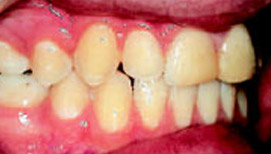

Рис.3:Обратное резцовое перекрытие

Рис.5: Через 3 дня после начала лечения

В процессе лечение в результате одновременного перемещения зубов – протрудирование верхних и ретрудирование нижних резцов – нормализация смыкания зубов достигается за очень короткое время. Даже при врожденной патологии достаточно обычного режима ношения аппарата - всего два часа днем и всю ночь.